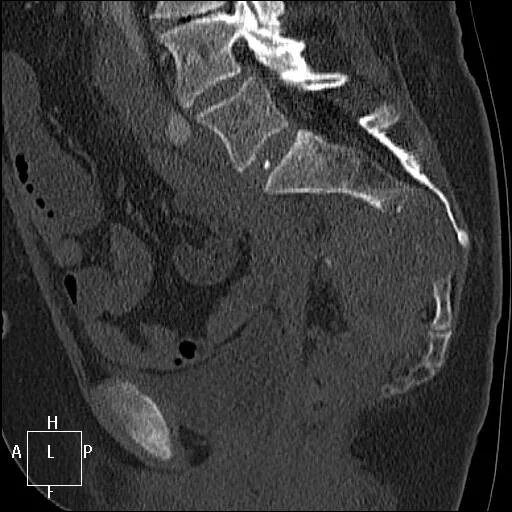

Метастазы в крестце